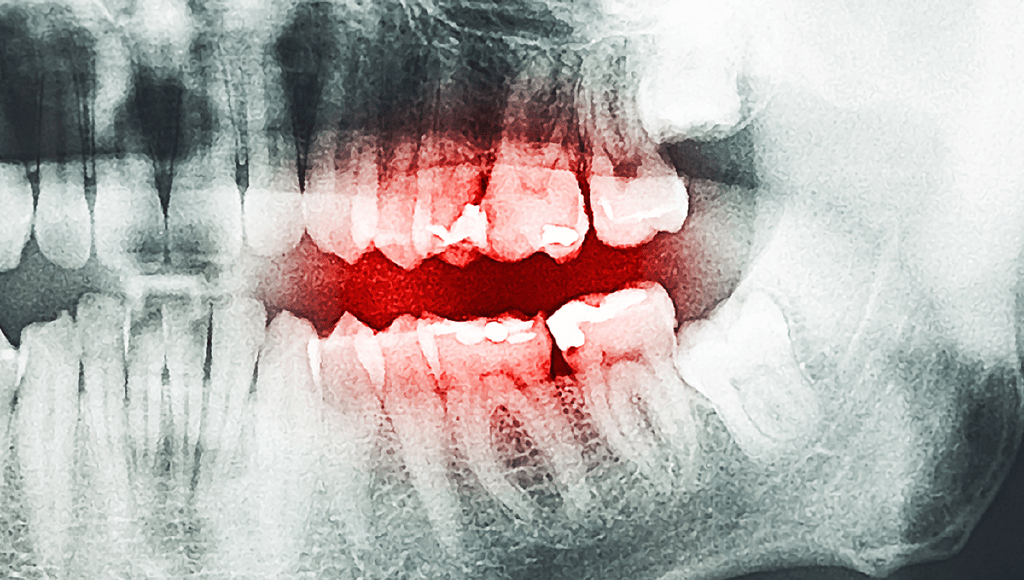

The Strange Exploding Teeth Epidemic Of 19th Century America

"All at once a sharp crack, like a pistol shot, bursting his tooth to fragments".